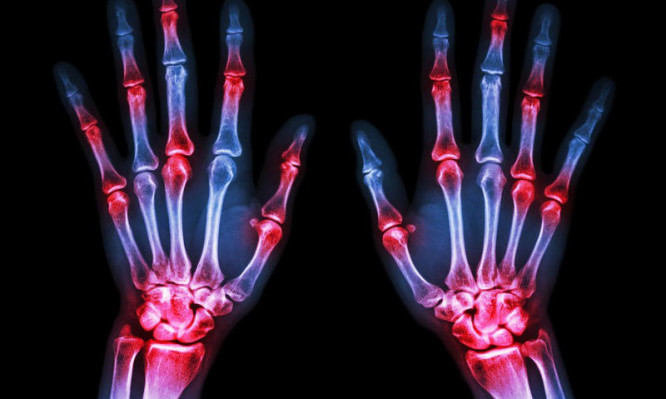

Αναφερόμενοι σε άτομα μεγαλύτερης ηλικίας , π.χ στην ηλικία των 60 ετών, η πιθανότερη αιτία του πόνου στις αρθρώσεις είναι η οστεοαρθρίτιδα, η οποία συνήθως προσβάλλει μία ή δύο αρθρώσεις και εξελίσσεται με εξάρσεις και υφέσεις. Η οστεοαρθρίτιδα είναι μια εκφυλιστική νόσος των αρθρώσεων. Μπορεί να προκαλέσει δυσφορία στον πάσχοντα όταν χρησιμοποιεί στο πλαίσιο της σωματικής κινητικότητάς του τις επηρεαζόμενες αρθρώσεις, όπως για παράδειγμα πόνο κατά το λύγισμα του γόνατος ή του μηρού ή δυσκαμψία στις αρθρώσεις των δακτύλων.